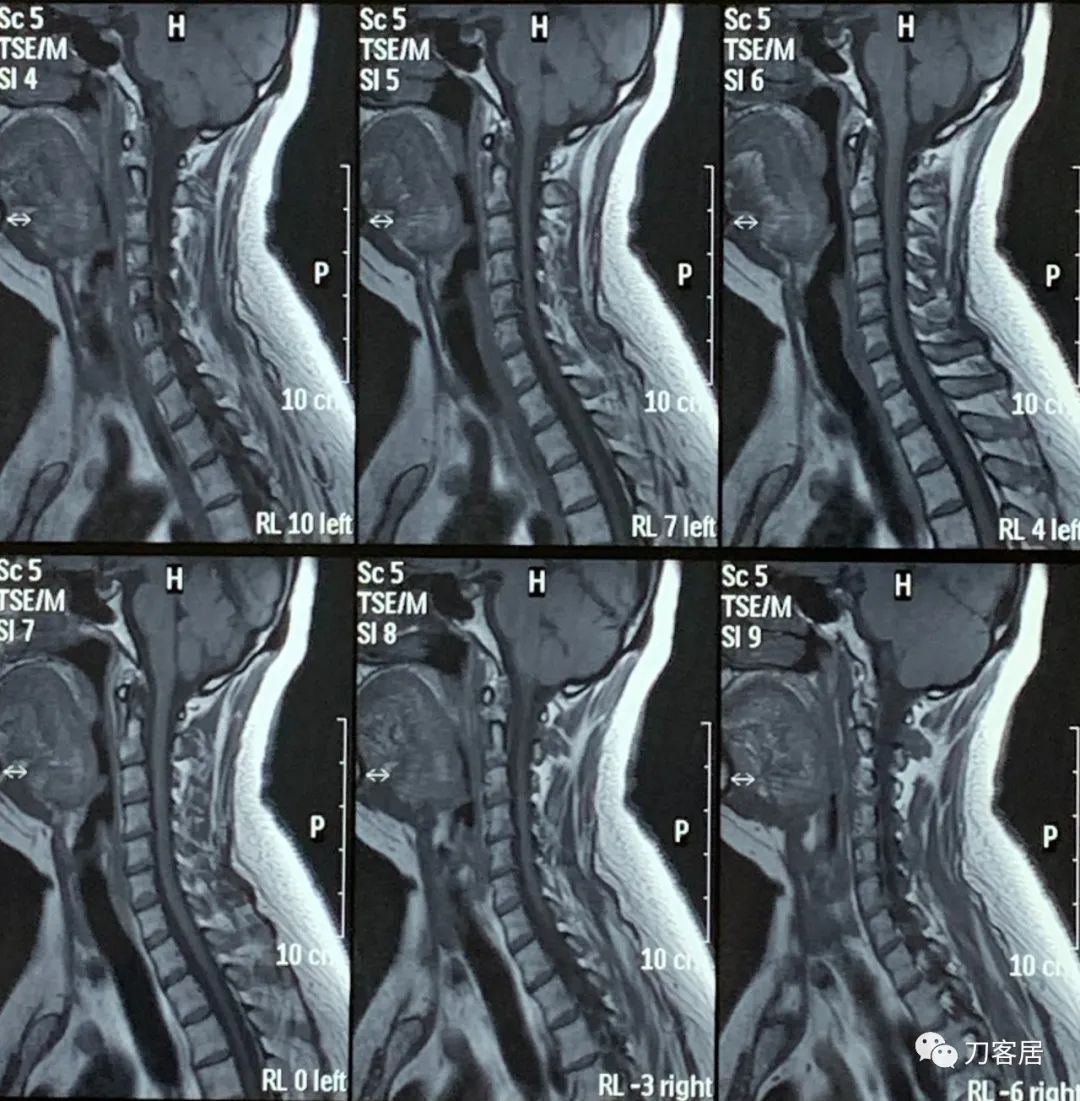

然后,2022年4月11日,患者又在当地另一家医院做了一次颈椎磁共振。

图27. 20220411平凉人民医院颈椎MRI01

图28. 20220411平凉人民医院颈椎MRI02

图29. 20220411平凉人民医院颈椎MRI03

图30. 20220411平凉人民医院颈椎MRI04

图31. 20220411平凉人民医院颈椎MRI05

图32. 20220411平凉人民颈椎MRI报告